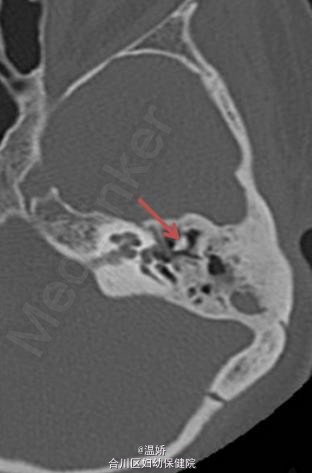

伴先天性耳畸形的范可尼贫血患者 1 例

先天性耳畸形

患者,女性,25 岁,范可尼贫血伴听力丧失。